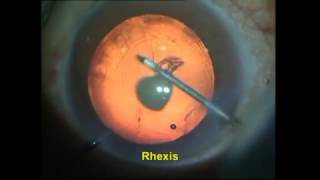

A Posterior polar cataract management video

A Posterior polar cataract management

A Posterior polar cataract management